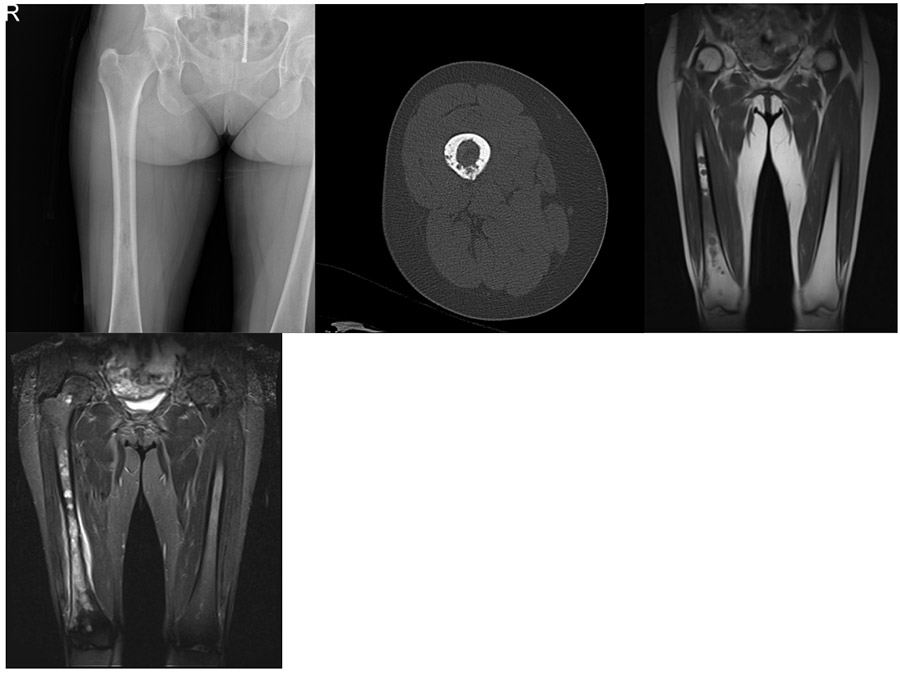

Before the surgery: X-rays and CT scans show lesions (lytic lesions) in the right femur, and MRI reveals widespread metastatic foci and edema.